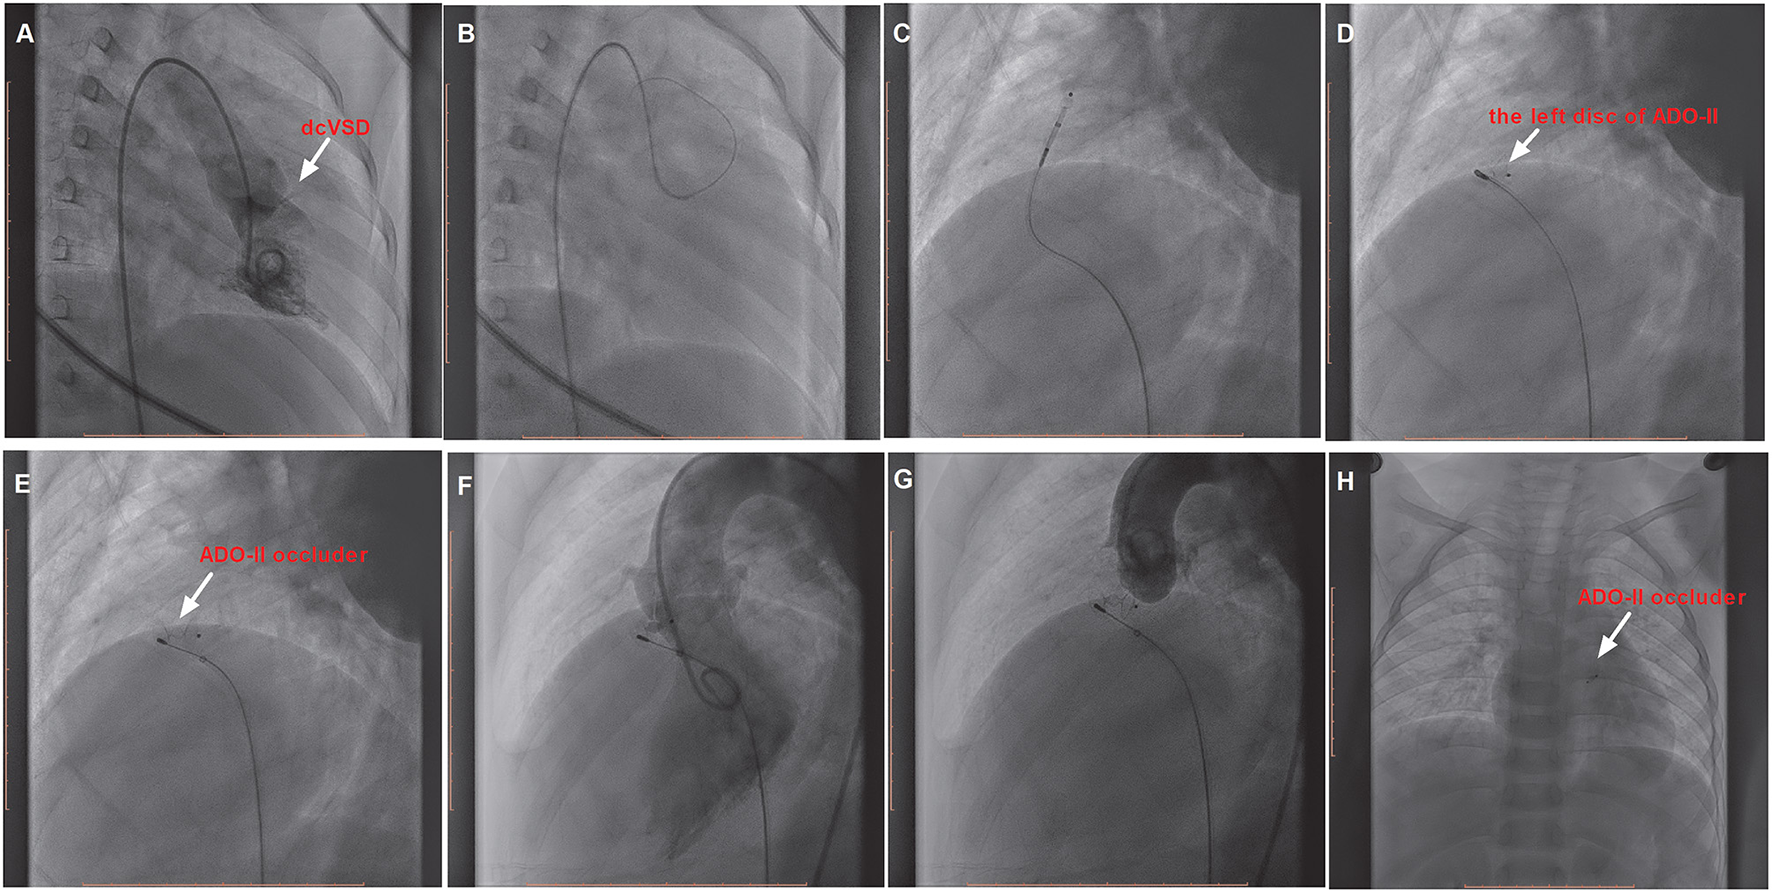

However, if the delivery sheath was difficult to pass through the defect, the snare (Starway Medical, Beijing, China) was used via the femoral vein to entrap the wire and pull it outside the body in order to establish a femoral artery vein loop (arterialvenous loop). Then, the delivery sheath was advanced into the left ventricle through the arterialvenous loop and the device was deployed antegradely from the venous side (Figure 3). Both before deployment of the device and after releasing the device, repeated left ventricular and aortic root angiographies and TTE were performed to ensure that there was no RS and that the aortic valve was not affected.

Figure 3

The procedure of transcatheter closure of the dcVSD using the ADO-II device via the antegrade approach. (A) Confirms the location of the dcVSD (arrow) with left-to-right shunting on left ventriculography before the procedure. (B–E) Show the whole processes of the transcatheter technique. (F) shows the operational success and no significant RS by left ventriculography, and (G) Shows no AR after device implantation by aortography before releasing the occluder. (H) Demonstrates the good position and configuration of the released occluder under X-ray fluoroscopy. dcVSD, doubly committed subarterial ventricular septal defect; AR, aortic regurgitation; RS, residual shunt.